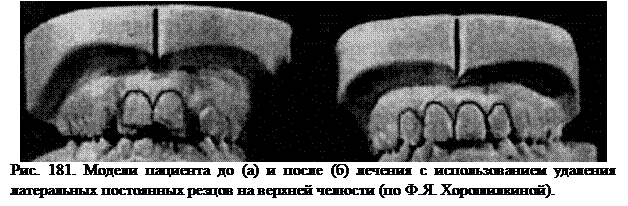

Если верхние боковые резцы шиповидные и нормализовать их форму путем протезирования не представляется возможным, такие зубы при тесном положении резцов лучше удалить в начальном периоде смены зубов. Затем удаляют временные клыки перед прорезыванием первых премоляров и вторые временные моляры для мезиального смещения зубов и уменьшения промежутков в зубном ряду. После установления постоянных клыков рядом с центральными резцами можно сошлифовать их острые бугры. При этом их положение рядом с резцами станет менее заметным для окружающих.